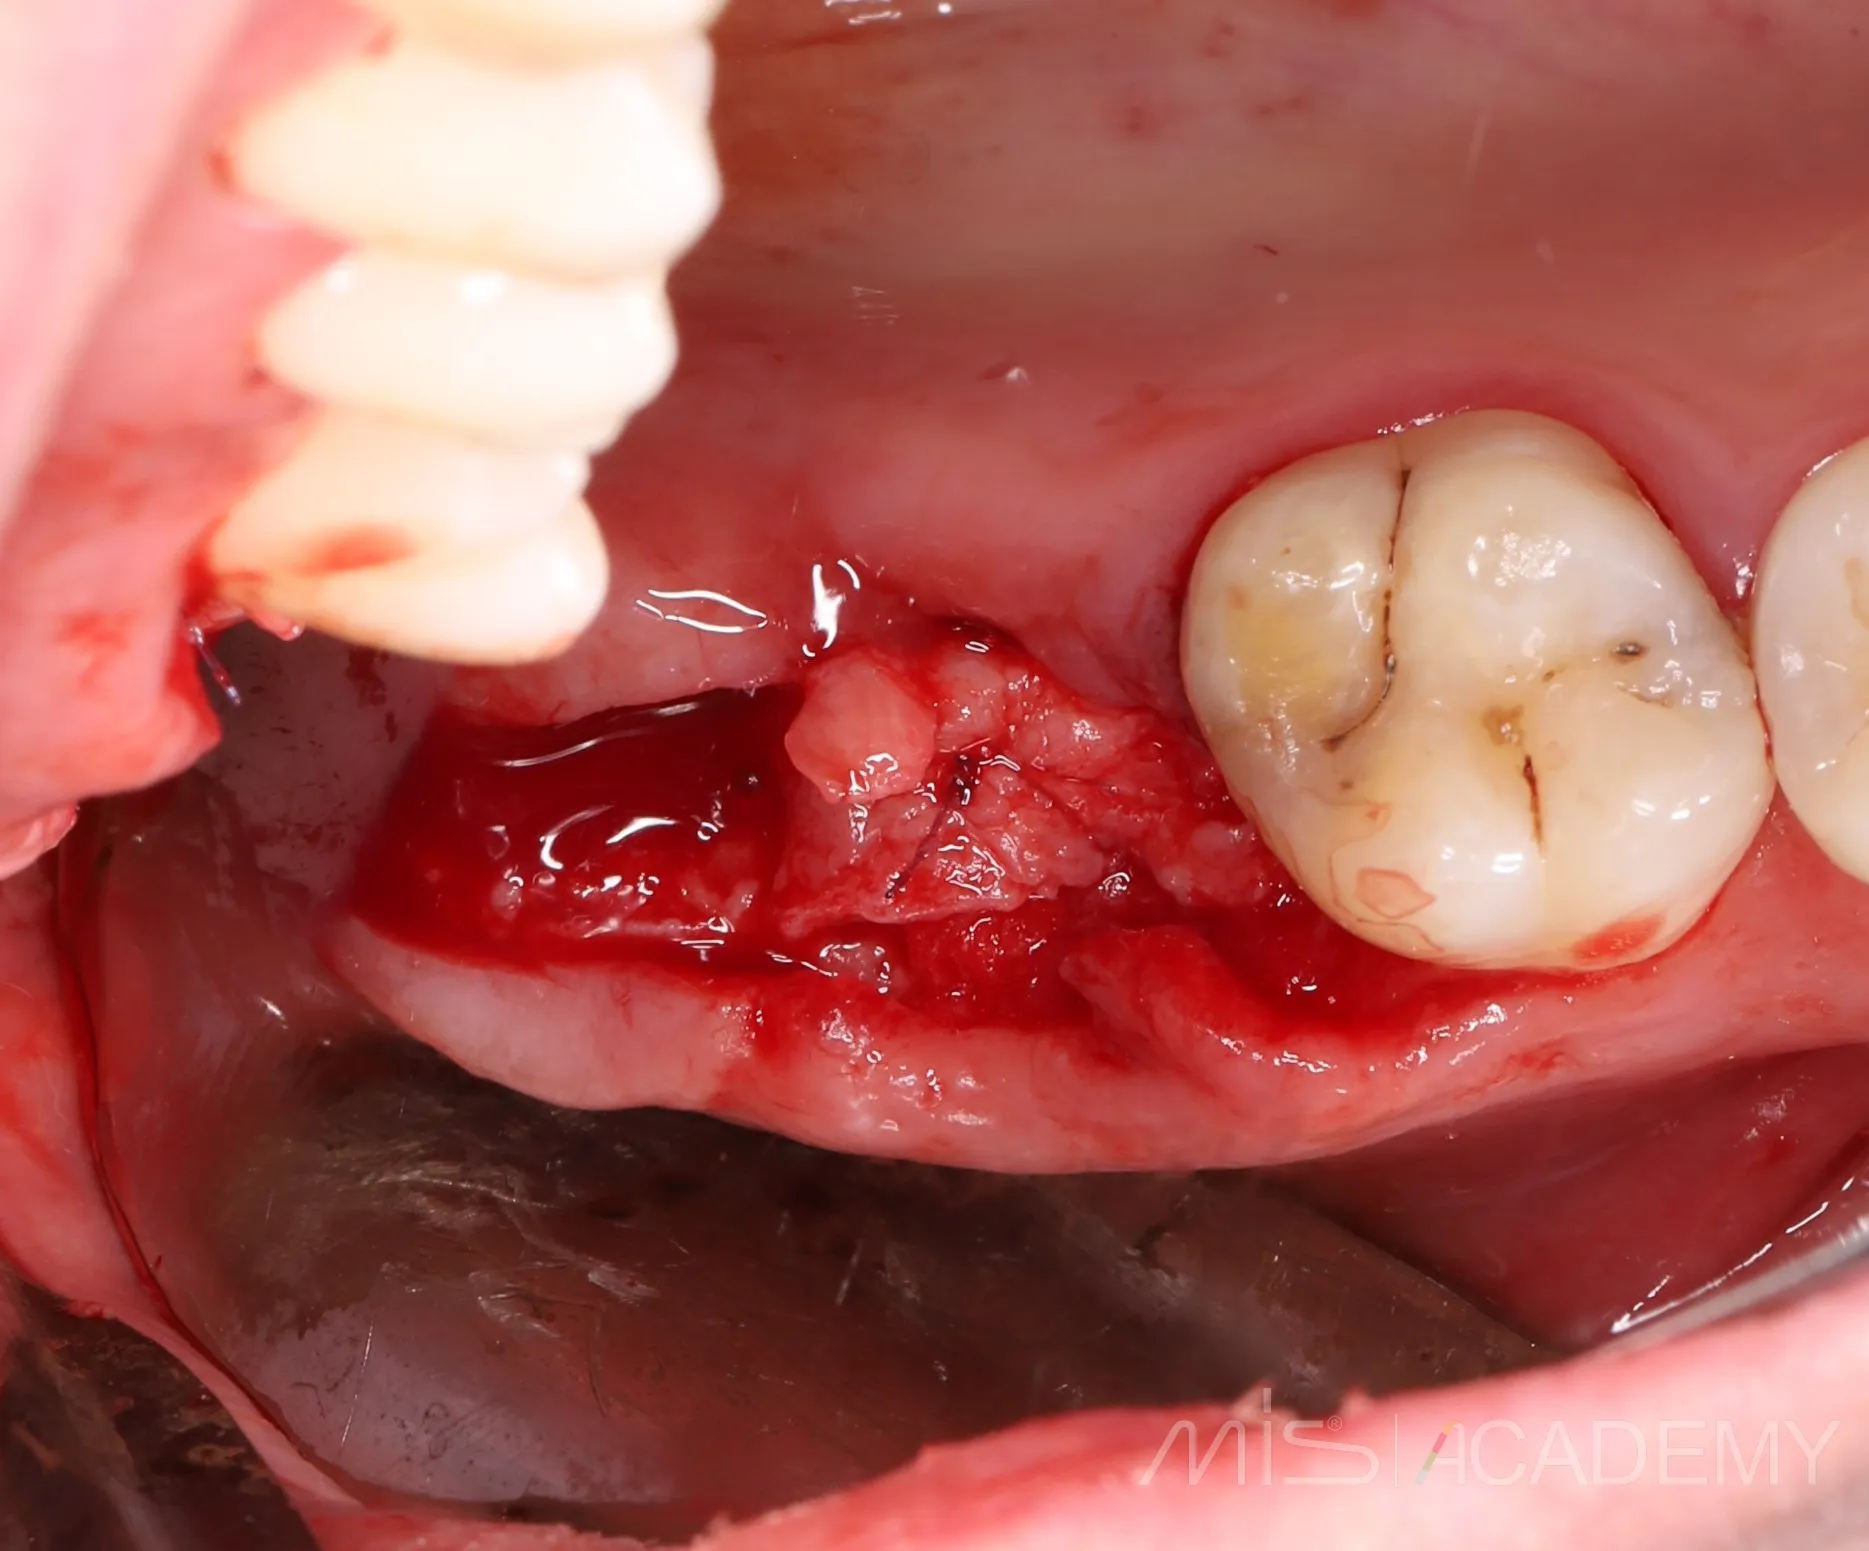

Да, я подсмотрел это способ у Артура Политова. Сейчас пациентка пришла на плановый осмотр с другой проблемой,

а зона соустья просто попала в кадр. Оказалось, что костный дефект самостоятельно закрылся и теперь там шикарные условия для ОСЛ. Ни разу не видел, чтобы соустья так закрывались. Что ж, будем теперь делать ОСЛ ..